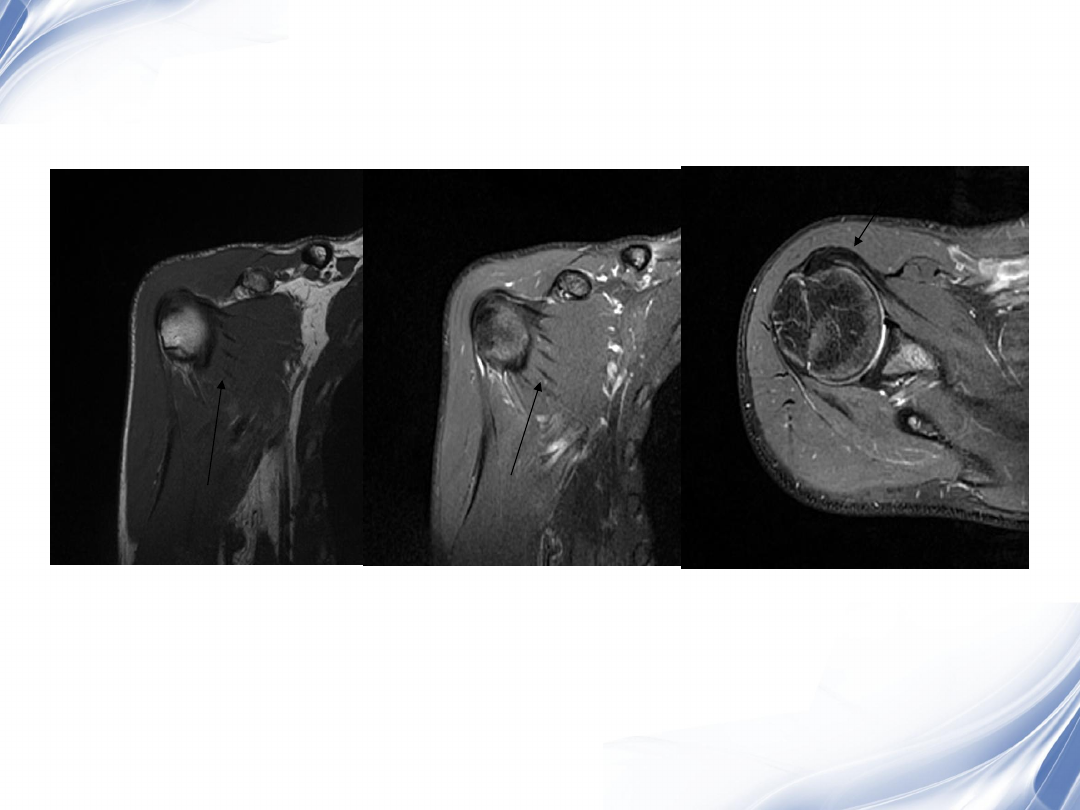

影像学检查

-MRI

最常用

斜冠状面、斜矢状面、横断面

常用的检查序列是

T1WI

T2

压脂

阳性率

95%

24

巨大肩袖损伤(冈上肌)

T2WI

36